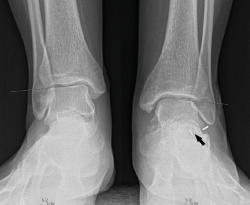

Primer caso (Figura 6)

Se trata de una paciente mujer de 27 años de edad, auxiliar sanitaria, con antecedentes de asma, depresión y psoriasis, que presenta un pie izquierdo plano valgo doloroso de 24° de valgo talar, por sinostosis calcaneoastragalina posterior. Dicha paciente presentaba una clínica de dolor en el seno del tarso y los tendones peroneos laterales. Como pruebas complementarias, se realizaron radiografías en carga de los pies y los tobillos, TAC y RMN del tobillo afecto. Se diagnostica de coalición tarsal de tipo 3 de la clasificación de Rozansky(26). Las articulaciones tibioperoneoastragalina y subtalar están preservadas clínica y radiológicamente. El balance articular es de: flexión = 45°; extensión = 15°; inversión = 5°; eversión = 0°. La escala de la American Orthopaedic Foot and Ankle Society (AOFAS) para el tobillo izquierdo presentaba un valor de 60 (20-35-5). Los ángulos radiológicos iniciales son: Moreau-Costa-Bartani interno = 143°; declinación talar = 25,8°; Meary = 9,9°; Kite = 25,5°; taloescafoideo = 54,6° (Tabla 1).

Segundo caso (Figura 7)

Se trata de una paciente mujer de 18 años de edad, higienista dental, sin antecedentes patológicos de interés, que presenta pies planos valgos bilaterales dolorosos, el derecho de 23° y el izquierdo de 21° de valgo, por sinostosis calcaneoastragalina media en ambos pies. En ella observamos básicamente una clínica de dolor en el seno del tarso, con déficit de movilidad de la articulación subtalar en ambos pies. Se realiza estudio mediante radiografías de los pies y los tobillos en carga y TAC de ambos pies (afectación bilateral). Radiológicamente, las articulaciones tibioperoneoastragalina y subtalar están preservadas. Se diagnostica de coalición tarsal de tipo 4 de la clasificación de Rozansky(26). El balance articular es de: flexión = 45°; extensión = 20°; inversión = 0°; eversión = 0°. La escala de la AOFAS para el tobillo derecho presentaba una puntuación de 62 (20-37-5). Los ángulos radiológicos iniciales son: Moreau-Costa-Bartani interno = 141°; declinación talar = 18,4°; Meary = 6,3°; Kite = 25,6°; taloescafoideo = 48,3°.

Figura 7. Radiografía del segundo caso: sinostosis talocalcánea media en ambos pies.